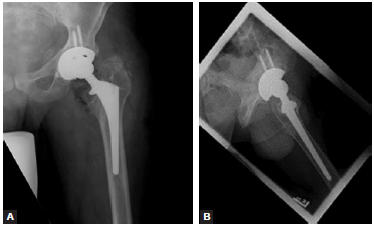

② 髋臼侧:同样如果股骨假体组件固定良好,而只有髋臼假体组件需要翻修,或者仅仅实施内衬的更换,则可以选择带偏心距的内衬以恢复股骨偏距,尤其是翻修相对早期的人工髋关节假体,无法通过颈长或颈干角的调整以获得良好的偏距重建时(图2)。

图2 偏心距髋臼内衬